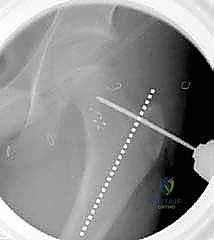

5. التدوير (Derotation)

هنا تكمن مهارة الجراح؛ يتم تدوير الجزء السفلي من عظم الفخذ (الساق بأكملها) إلى الخارج بالدرجة المطلوبة تماماً (عادة بين 20 إلى 30 درجة) لتصحيح الانحراف الأمامي المفرط وإعادة القدم إلى وضعية الاستقامة الطبيعية.

6. التثبيت الداخلي القوي (Internal Fixation)

لضمان التحام العظم في وضعه الجديد، يستخدم الدكتور هطيف نظام تثبيت عالمي يتمثل في صفيحة الشفرة الزاوية (AO 90-degree Blade Plate) أو مسامير وصفيحة مخصصة للأطفال. يتم إدخال الشفرة في عنق الفخذ، وتثبيت الصفيحة على جسم العظم باستخدام براغي معدنية قوية.